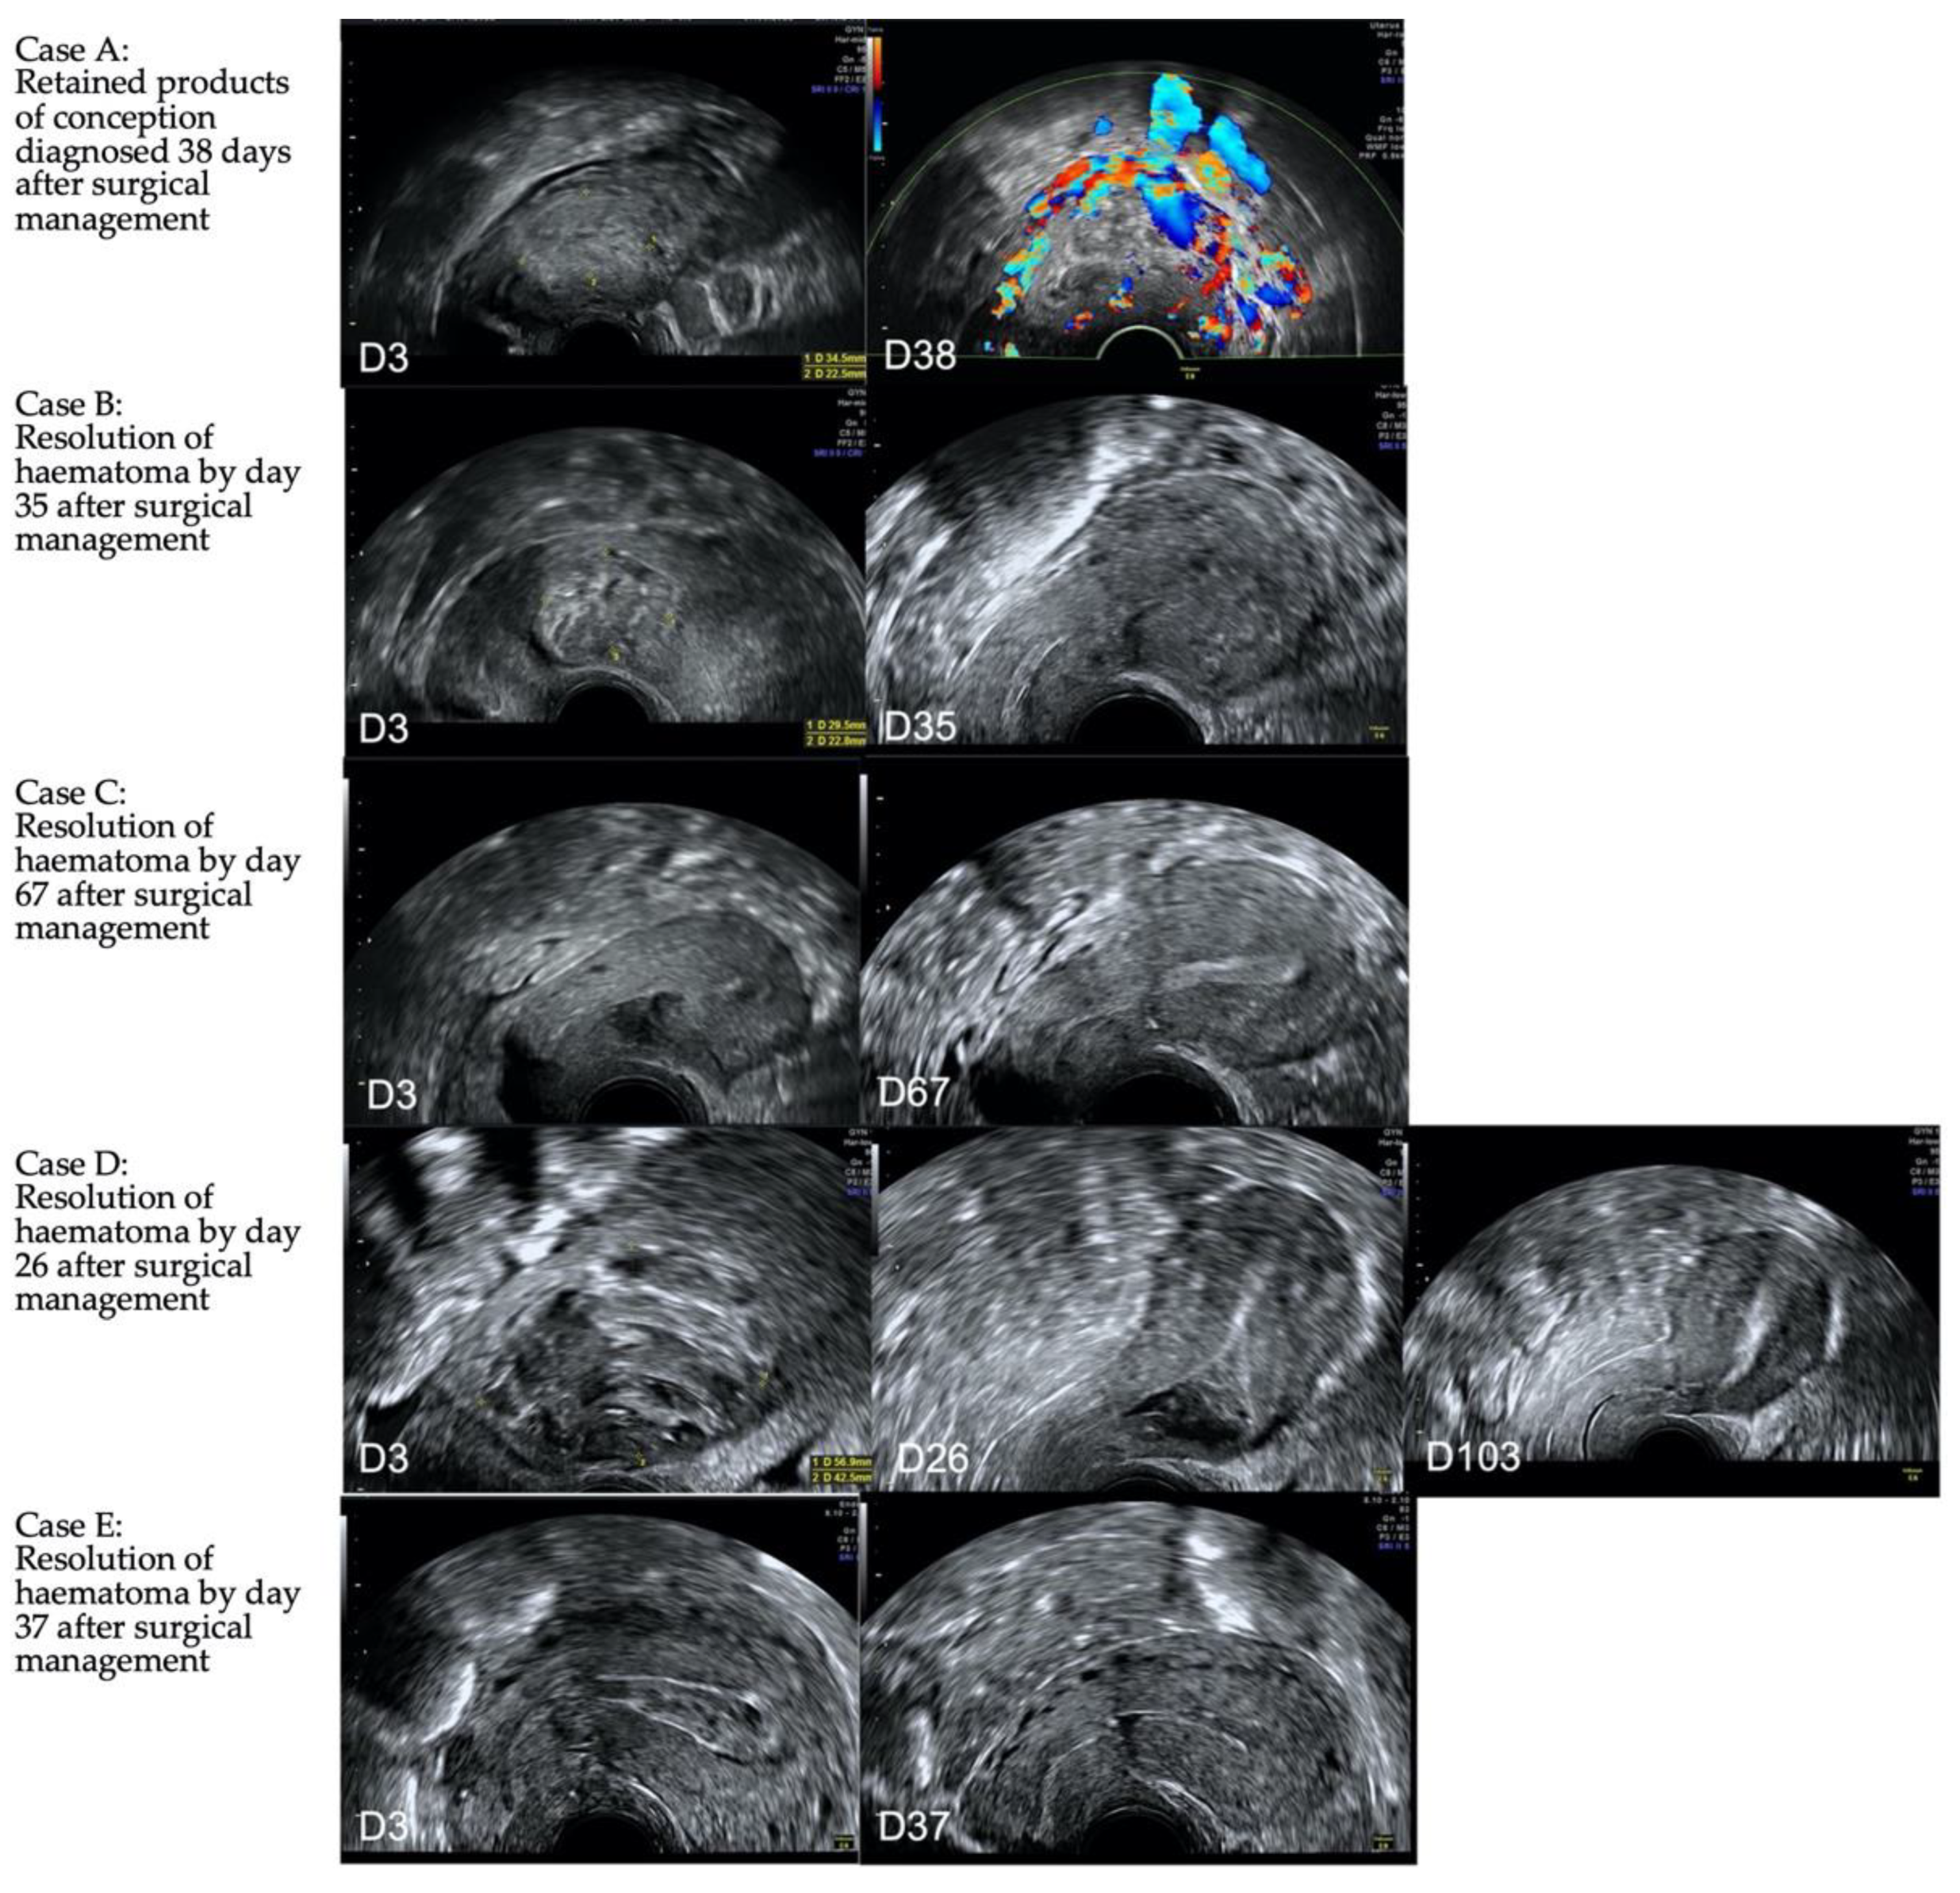

Following surgical management, formation of an intrauterine haematoma was expected, and in the majority of cases this resolved by the 6-week follow up. In one patient, RPOC was present (Figure 5).

Figure 5. Longitudinal ultrasound images of five cases (case AE) managed surgically with cerclage and balloon. The initial image was obtained on day 3 (D3) at the time of cerclage removal, and subsequent images are obtained between day 26 and 103 post surgical management. In 4/5 the haematoma present on day 3 resolves, whereas in one (A), retained products of conception is diagnosed at day 38 post surgery.